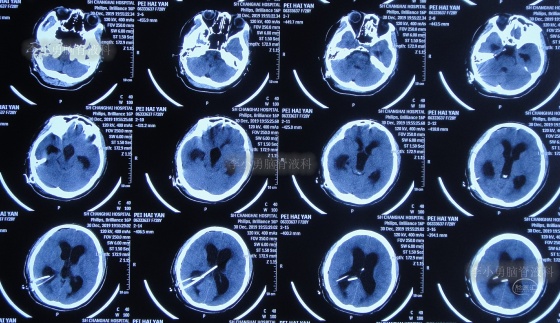

脑积水第1次脑室腹腔分流术后14年,即第2次脑室腹腔分流术后13年,即第3次脑室腹腔分流术后3个月半,5次就诊于给予手术的医院但仍脑积水,颅内感染情况下于2020年4月11日,住入李小勇脑脊液科,入院时:头晕伴视物不清,呕吐,睡眠差,头部有手术瘢痕(图-13);入院时头颅CT示脑积水,脑室内有3根管(图-14)。

图-13:2020年4月11日入院时

图-14:2020年4月11日入院时头颅CT

入院后4天即2020年4月15日,拔除了原3根分流管+两侧脑室外引流术(图-15)。

图-15:2020年4月15日头颅CT

图-16:2020年4月16日头颅CT